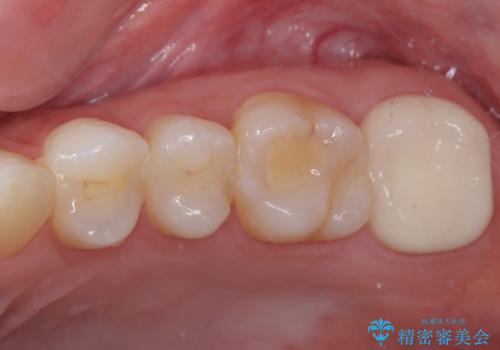

- 大学病院で「詰め物の下に虫歯がある」と言われたことを主訴に来院された患者様です。たまにしみる感じがするとのことでした。

レントゲン上で詰め物とご自身の歯の間に隙間を認めました。

拡大鏡視野下で詰め物と虫歯の除去を行い、詰め物の範囲が大きかったためオールセラミッククラウンに適した形に整えました。